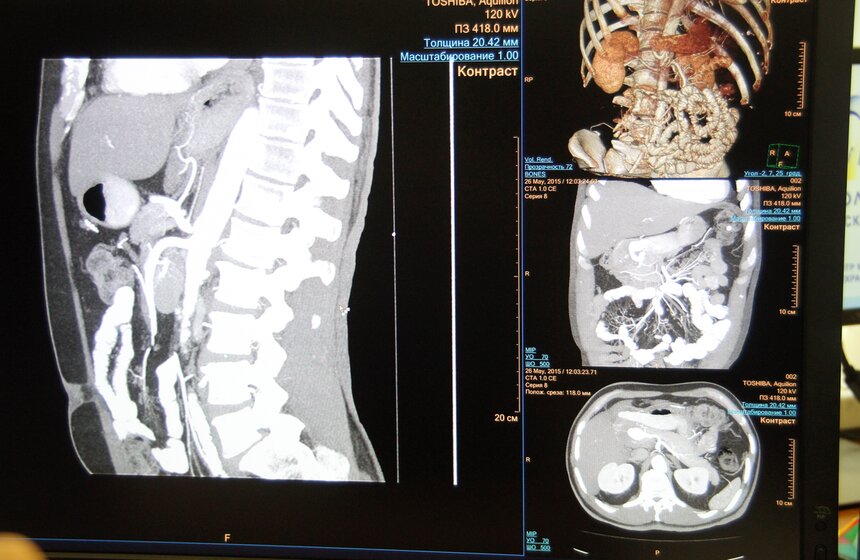

Сергей Собянин посетил Научно-практический центр медицинской радиологии, где ознакомился с работой Единой радиологической информационной системы (ЕРИС).